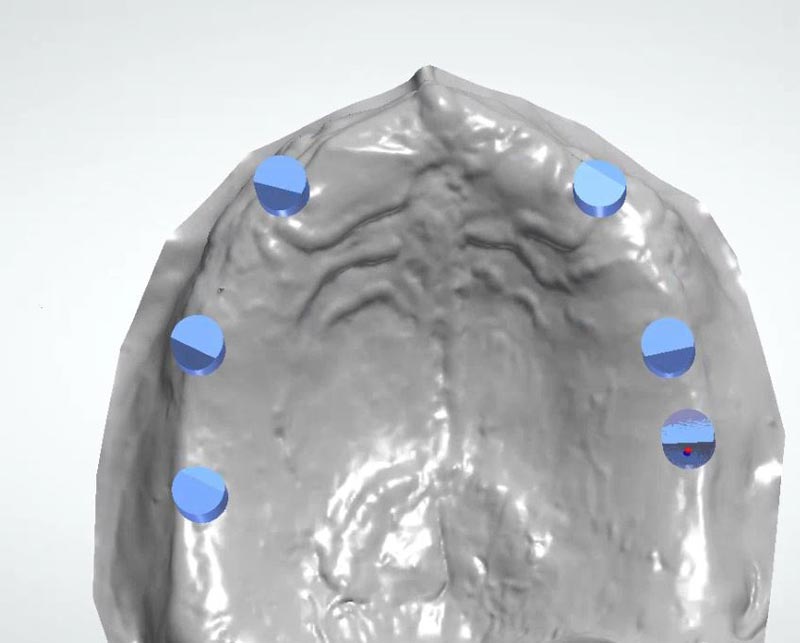

Scan Body per MUA virtuali inseriti da pianificazione

Modellazione 3D della guida chirurgica scomposta

Guida chirurgica primaria su modello stereotipato, la guida è realizzata in titanio e colorata tramite tecnica di anodizzazione

Parte secondaria della guida chirurgica, che si lega alla prima tramite dei mua montati per questo scopo